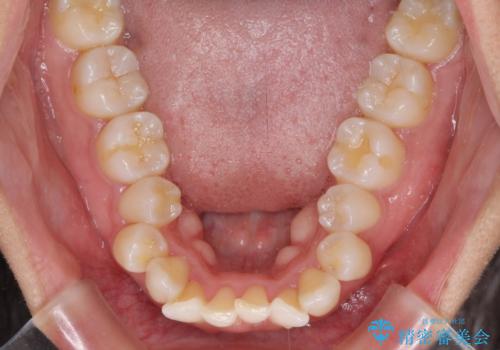

- 下唇が突き出るような口元の突出感が気になるとのことで来院された患者様です。

上下顎ともに前突した歯列であったので、上下ともに左右の第1小臼歯4本を抜歯し、ワイヤー装置にて矯正治療を行うこととしました。